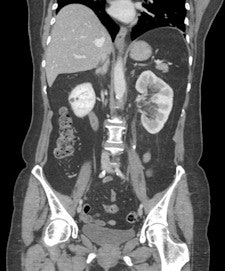

Figure 4 is a CT scan performed for a clinical diagnosis of complicated diverticular disease. The coronal CT scan showed the left-sided ureteric calculus with hydronephrosis. Within a couple of hours, the patient was having a nephrostomy for an obstructed septic kidney. Whilst Hurry Fenwick would be astonished by our ability to perform a coronal CT to show the ureteric calculus and then to drain a compromised septic kidney, I think he would be concerned about the clinical confusion of diverticular disease and renal disease. Radiology works best following accurate clinical assessment. The role of radiology is to confirm and support a clinical diagnosis, and not to rule out less-likely diagnoses by an indiscriminate use of complex radiological examinations.